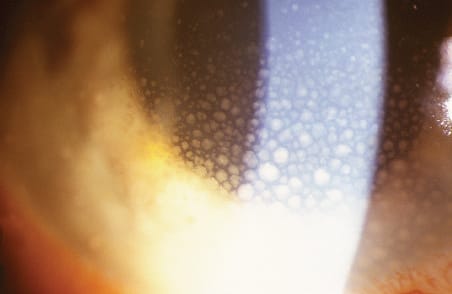

Figure 2. Extensive peripheral necrotizing retinitis and periarteritis in an immunocompetent patient with ARN.